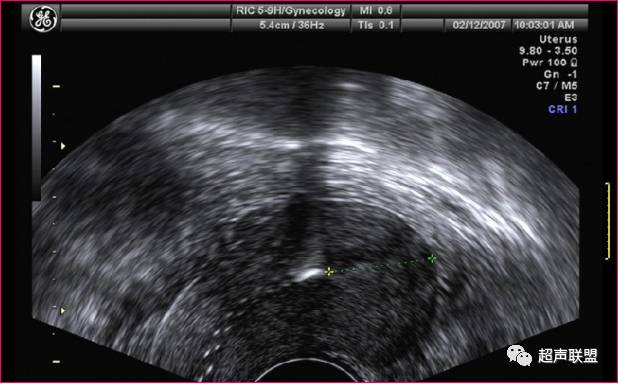

(五)、IUD变形、断裂、横置

IUD在宫腔内正常位置的变形较少见。大多数属于IUD低置,为了适应变化的环境而发生IUD变形。常见不锈钢圆环、VIUD变形。子宫纵断面,圆环两彗星状声影平面与宫体冠状面成角,出现一个彗星状声影平面和一个强光带图像,或两彗星状声影之间夹有强光带图像。子宫横断面,圆环变形呈椭圆形、“8”字形强回声。VIUD变形呈上开口菱形或不规则较强回声。另外对带有横臂的IUD,显示横弩不能充分展开时,将影响避孕效果及出现腹痛、阴道出血等症状。IUD横置、倒置多见于带器妊娠,人工流产时未取出IUD所致。

节育器变形

宫腔内节育环(IUD)变形.

(经阴道超声)